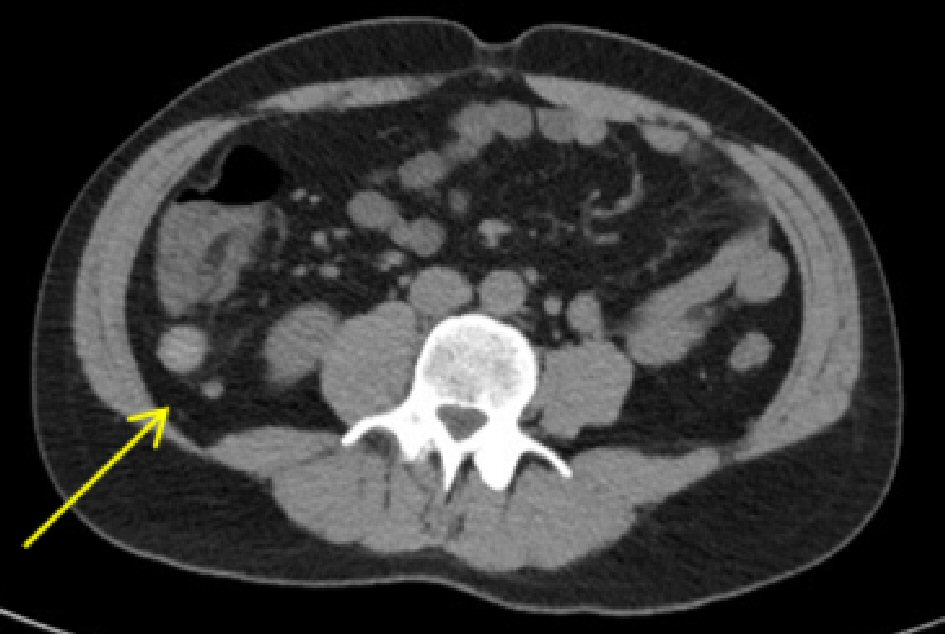

A 35-year-old man presented to a local emergency department following three episodes of nighttime upper abdominal pain. His past medical and surgical history was notable for a left inguinal hernia repair during childhood and a vague history of gastritis for several years. Computed tomography (CT) imaging revealed a single gallbladder calculus without radiographic evidence of cholecystitis and an incidental mass (3.7 × 1.9 × 1.6 cm) at the tip of the appendix (Fig. 1).

![]() Click for large image | Figure 1. Abdominal CT imaging demonstrated a 3.7-cm mass at the appendiceal tip (arrow). CT: computed tomography. |